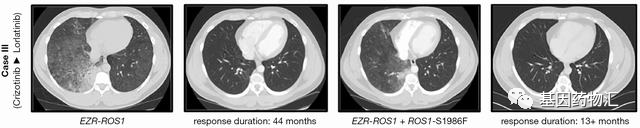

案例二:44+13个月

这位男性患者非常年轻,32岁,只有非常轻微的吸烟史(<1 包年),诊断为晚期肺腺癌,双肺及腋窝淋巴结都有转移病灶。FISH检查提示存在ROS1重排(67.5%)。

患者一线便接受了克唑替尼治疗,持续缓解整整44个月!后续在右下肺发现了新的病灶,并重新接受了基因检测(二代测序),并确认了耐药突变EZR-ROS1融合以及ROS1-S1986F突变。

患者二线接受了劳拉替尼治疗,至当前随访13个月,疗效仍在持续。